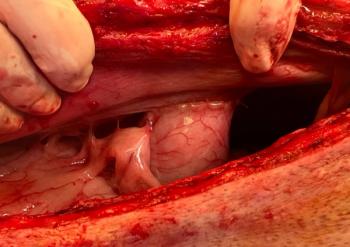

There are many methods for surgically managing idiopathic canine chylothorax, but diagnostic information collected from an individual dog will guide the specific approach.

This surgical method can help manage a life-threatening disease